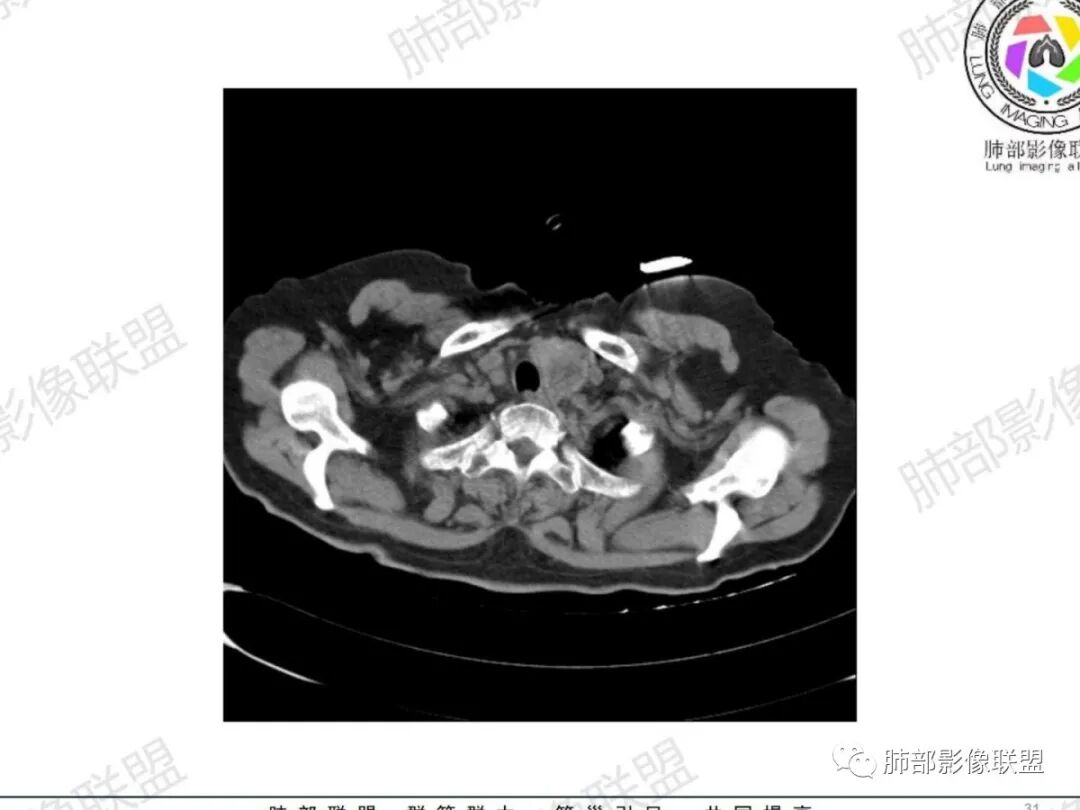

从病史提示:甲状腺占位、气管占位、肺部炎症

左肺下叶背段见树芽征

甲状腺左叶结节边界不太清楚